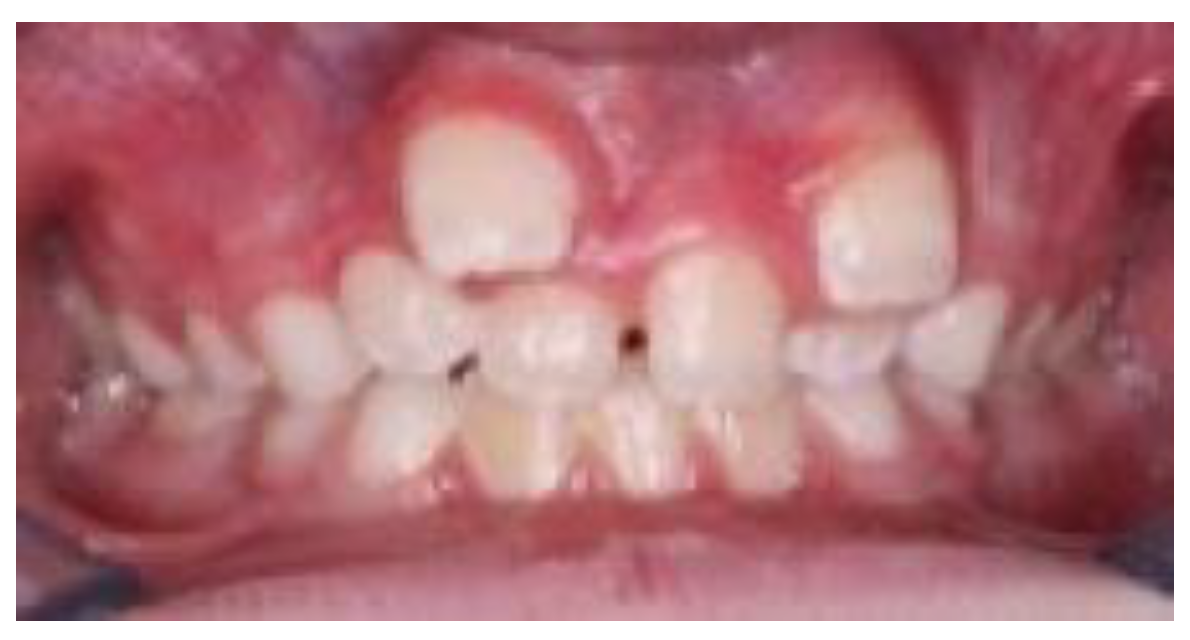

Accurate diagnosis and precise localization are indispensable for successful treatment planning and prevention of secondary complications [2,18]. Traditional two-dimensional radiographic methods [33], such as panoramic (orthopantomogram) and periapical radiographs (Figure 3), remain valuable as initial diagnostic tools that often fail to provide sufficient information regarding the three-dimensional relationship between ST and adjacent anatomical structures [33,34].

Figure 3. Orthopantomogram showing a supernumerary tooth located between the left mandibular canine (tooth 3.3) and the left mandibular first premolar (tooth 3.4).